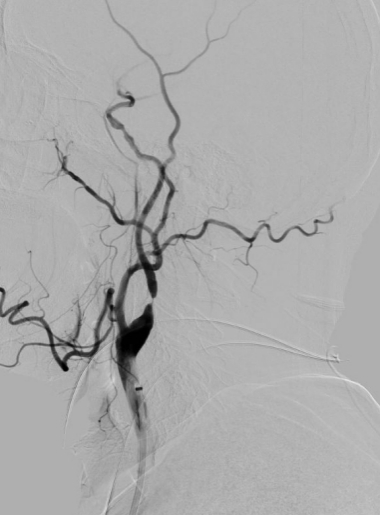

脑血管造影是目前脑血管检查的金标准,是通过动脉插管,使用造影剂显影完成脑血管检查的一种微创方法。其特点:简单、方便、安全、准确、创伤小。我院从2009年开始开展脑血管造影检查,目前开展经桡动脉、股动脉两种路径完成脑血管造影及治疗,桡动脉路径大大减轻患者的痛苦。目前开展的治疗手术:颅内外血管球囊扩张成形术、支架置入术、动脉瘤栓塞术、急症溶栓、取栓术,对于出血性脑血管病患者开展了微创血肿清除术。每年造影检查量约500例左右,治疗量约100例左右。介入技术水平走在了全市前列,取得了广大患者的好评。

图片1.jpg  图片2.jpg

经股动脉入路造影                                                               经桡动脉入路造影